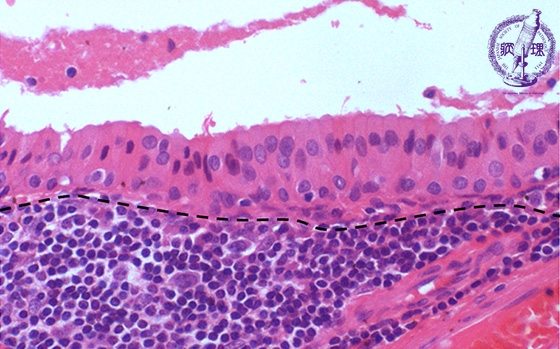

唾液腺腫瘍(ワルチン腫瘍)ミクロ像(HE強拡大)

ミクロ像(HE強拡大):腫瘍細胞は、好酸性顆粒状の細胞質を有するオンコサイトである。腔に面する高円柱状細胞とその下の立方形細胞が2列に並んでいる。間質(点線下方)は、リンパ性組織である。